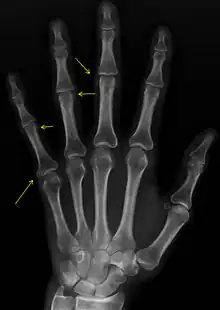

CREST syndrome (calcinosis and sclerodactyly)

Calcinosis

CREST causes thickening and tightening of the skin with deposition of calcific nodules ("calcinosis").